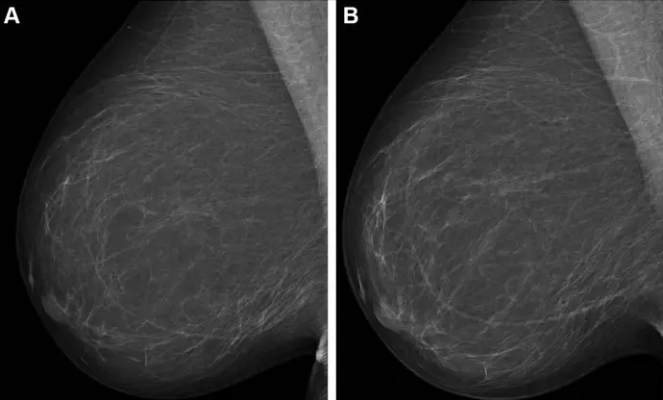

Full-field digital mammograms (right mediolateral oblique view) in a 59-year-old woman show (A) the screening mammogram obtained during the study period and (B) the screening mammogram obtained in the subsequent screening round. The first screening mammogram (A) had a very low combined risk score (lowest 0.1%) as determined by the combination model with texture risk and the examination score. The woman was not recalled and did not receive a breast cancer diagnosis throughout the 5-year follow-up. Image courtesy of Radiological Society of North America